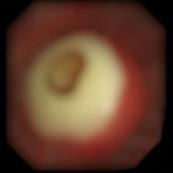

牟向东主任告诉我们,当时门诊初步诊断这位患者是支气管内阻塞导致的肺不张。「我们因此给患者进行了全麻下支气管镜检查,发现他的右肺中间段支气管被肿物完全阻塞,并且有较多黏痰,反复吸痰治疗后,应用激光烧灼肿物,然后应用冷冻探头将中午取出;其后又发现右肺中叶支气管已完全被结石堵塞,随即应用高能激光反复治疗,然后综合应用冷冻、电烧、电圈套器等方法,终于将这块肿物分次取出,并留取了组织送检病理。后来的病理报告显示,该患者的右肺中叶支气管肿物是『肺错构瘤』。肺错构瘤长在支气管里这种情况极为少见,属于罕见病,绝大多数都是长在肺内。」

图为长在患者支气管里的肺错构瘤

图片由牟向东主任提供